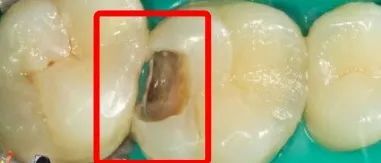

常爸找来了两个案例,一起来看一下:比如,这是从外面看,牙缝里稍稍有点黑,不仔细看还发现不了。

图片

我们换一个视角,从里面看,是不是黑的区域明显更大一些了?

医生处理之后,龋坏部分完全暴露出来,简直是触目惊心,外面看起来好好的牙,实际上里面已经黑成一坨了。